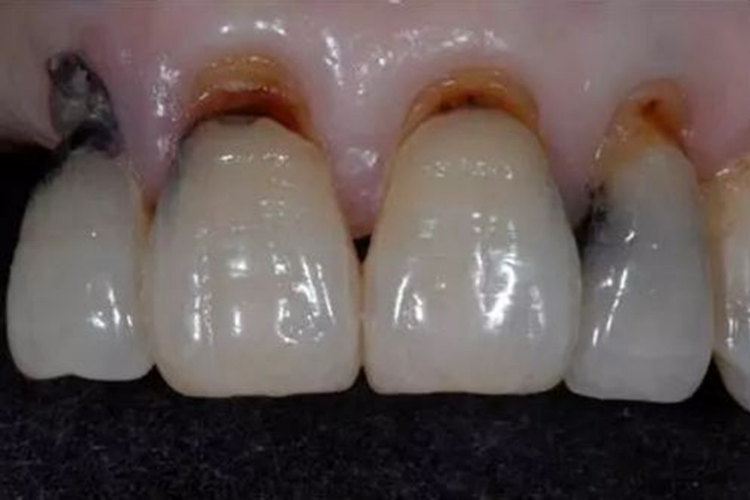

牙齿楔状缺损与年龄相关,年龄愈大,楔状缺损愈严重。患者多有横向刷牙习惯。罹患的牙齿为多颗甚至全口。患牙一般没有牙周病。多发于前磨牙,尤其是第一前磨牙,一般伴有牙龈退缩。典型的楔状缺损由两个平面相交而成,有的由三个平面组成,缺损边缘整齐,表面坚硬光滑,可出现不同程度的着色。较浅的缺损可无症状,也可发生牙本质过敏症。深至牙髓的缺损可伴有牙髓及根尖周病的临床表现。